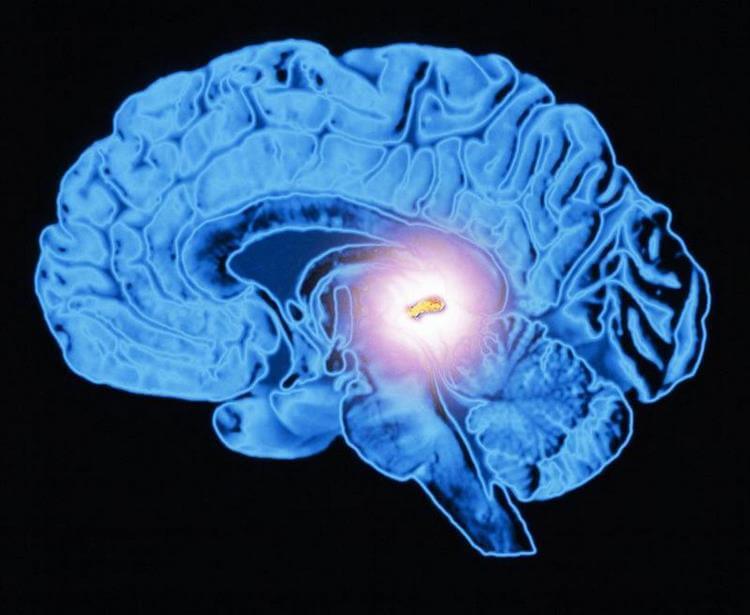

Мелатонин вырабатывается эпифизом (шишковидной железой)

Рассматривая вопрос о том, как вырабатывается мелатонин, чаще всего связывают его производство с эпифизом или шишковидной железой. Под действием солнечного света аминокислота триптофан в организме преобразуется в серотонин, который ночью уже превращается в мелатонин. После его синтеза в эпифизе мелатонин попадает в спинномозговую жидкость и кровь. Таким образом, для всех этих преобразований необходимо ежедневно по полчаса-часу проводить на улице в светлое время суток.